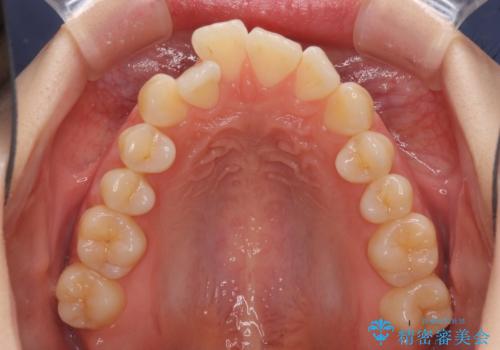

気になるデコボコとオープンバイト インビザラインでの矯正治療

- 前歯のデコボコと上下が開いていることを気にして来院された患者様です。

いわゆるオープンバイトは、インビザラインによる治療が適しているため、インビザラインにて治療を行うこととしました。

オープンバイトは容易に後戻りを起こすため、少しでも後戻りリスクを軽減するために舌癖改善のトレーニングをしっかりと行っていただきました。